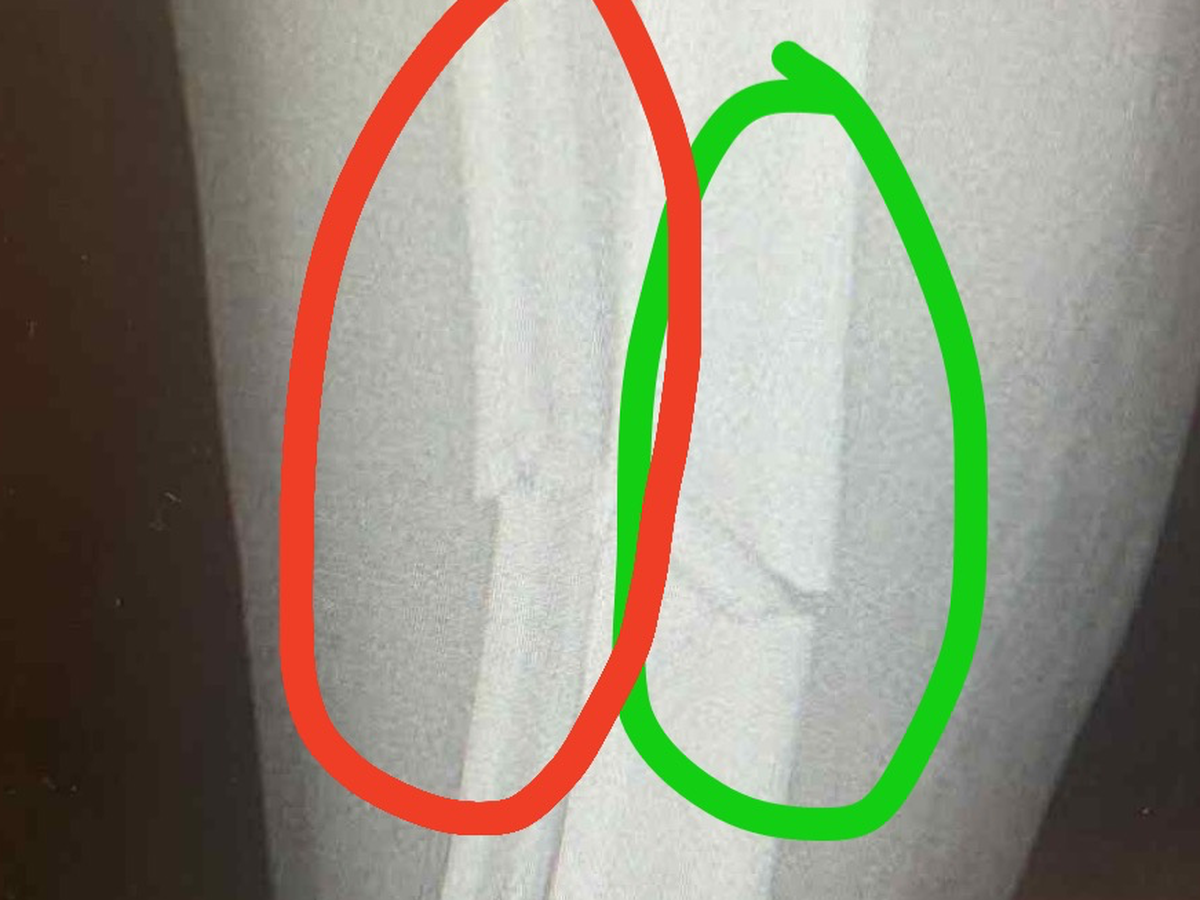

On Saturday 25th October, one of our men’s teams were playing a league match against Montpellier Reserves. During this match one of our players, Josh Swales, unfortunately suffered a triple leg fracture during a horrific tackle. The match was abandoned and Josh was rushed to hospital. In hospital Josh was put into a cast and transferred to Gloucester Royal Hospital. On Monday 27th October, Josh had surgery to insert a metal rod and 4 screws into his leg. On Thursday 30th October, Josh was discharged with crutches to continue recovery from home. He was told he would be unable to put full weight through the leg for at least 6 weeks, be off work for 8-12 weeks and out of any exercise for 4-6 months.